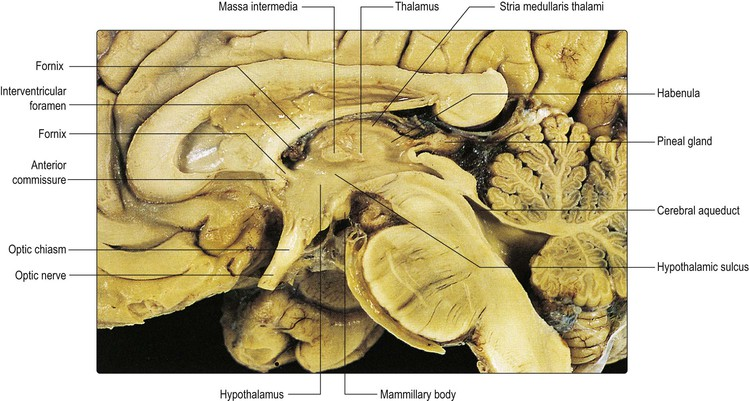

Diencepathon

Thalamus

Interthalamic mass

Striae medullaris thalami

Habenular nucleus

Pineal gland

Hypothalamus

Hypothalamus

Anterior commissure

Lamina terminalis

Thalamus

Optic chiasm

Infundibulum and pituitary gland

Tuber cinereum

Mammillary bodies

Cingulate gyrus

Fornix

Striae medullaris thalami

Pineal gland

Posterior commissure